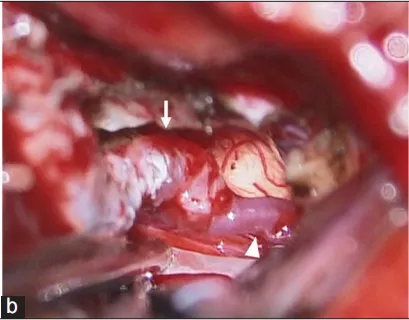

然而,术后第11天,随访CTA显示对侧VADA无症状扩大(图3c-d)。教授通过外侧枕下入路近端夹断右侧VADA(图4)。同时,通过颞下入路进行颞浅动脉-小脑上动脉旁路术,以保持后循环中的脑血流(图5)。术后双侧VADA被切除,康复后约1个月出院且术后1年随访期间病情平稳。

图4b:术中右侧颞浅动脉(箭头)-SCA(箭头)旁路术的表现。旁路中断时间为28 min。

图4c:术中小脑后下动脉近端夹闭(箭头)。

图4d:术中右侧椎夹层动脉瘤及远端至脑干穿支(箭头)。